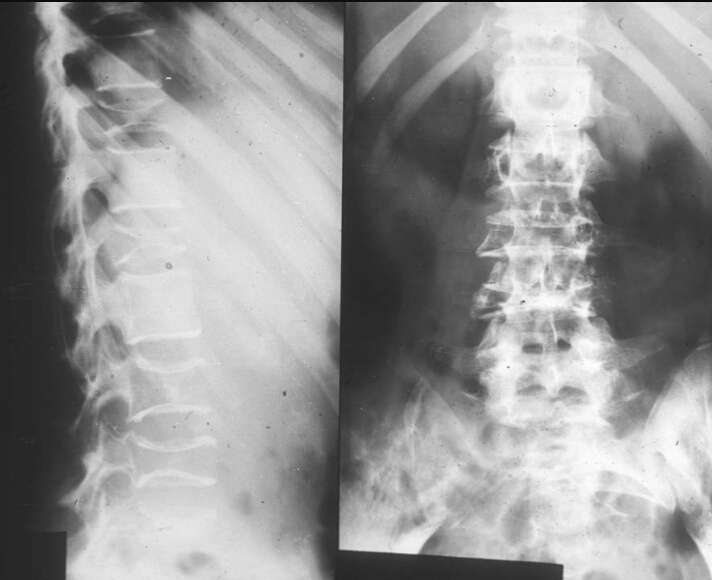

Patient is a 60 year old male has and has been complaining of pain, unexplained weight loss and recurrent respiratory infections. You take this xray and labs. Elevated ESR and M spike. What are the findings? Diagnosis?

Osteoporosis/osteopenia, soap bubble appearance

Multiple myeloma